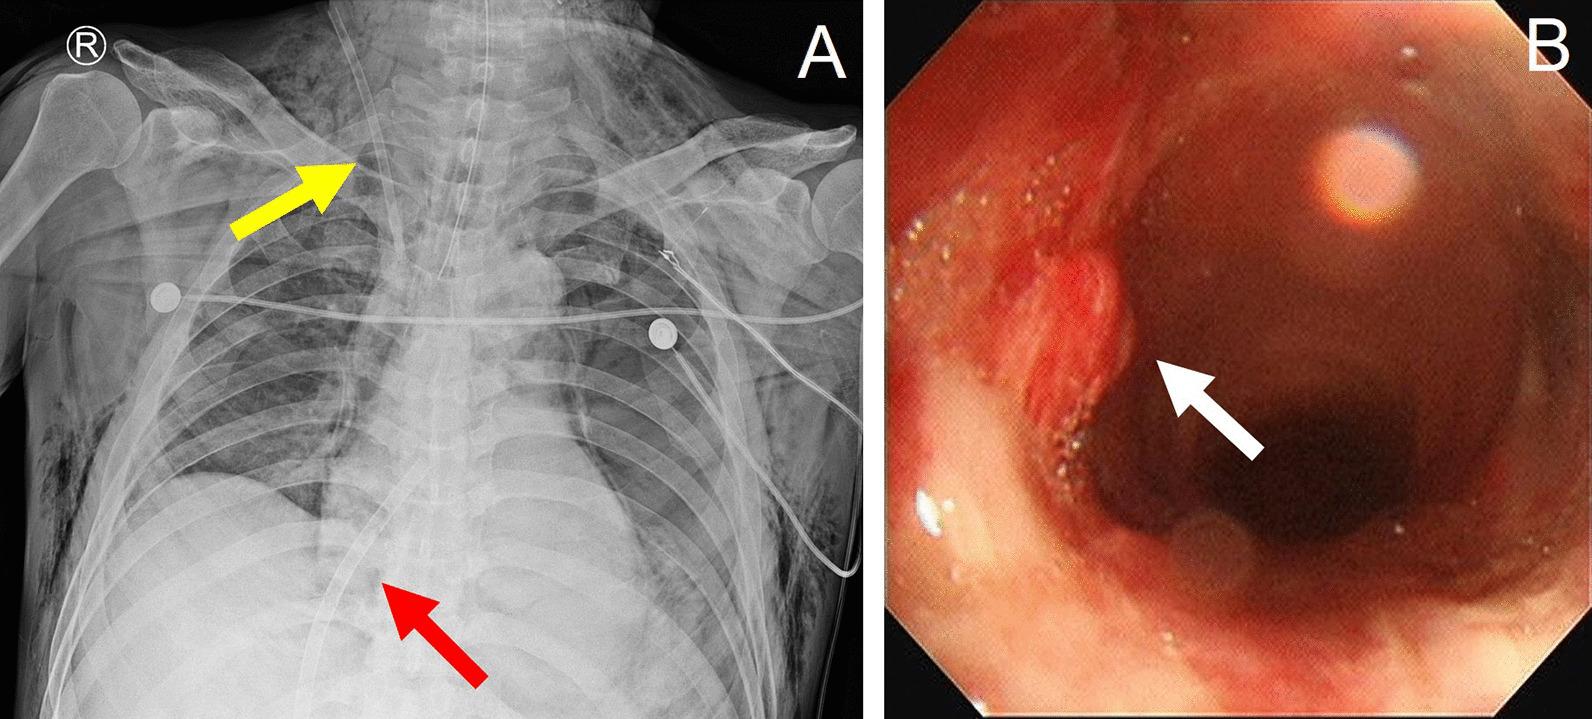

We describe the case of a 66-year-old man with tracheal rupture with thyroid cartilage fracture due to cultivator handle who was treated with veno-venous ECMO. This case reflects the role and limitations of veno-venous ECMO, in which patient survival was possible with a bi-femoral configuration while also ensuring a clear airway.

我们描述了一名 66 岁男性患者的病例,该患者因手扶耕耘机把手导致气管破裂和甲状软骨骨折,接受了静脉-静脉 ECMO 治疗。该病例反映了静脉-静脉 ECMO 的作用和局限性,其中双股静脉 ECMO 配置可确保患者存活并保持气道通畅。